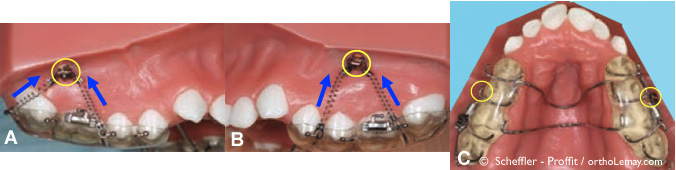

Fig. 1 – Exemples de mini-vis d’ancrage (cercles jaunes) utilisées pour servir d’ancrage à des ressorts qui “intrudent” ou remontent les dents postérieures (flèches bleues) et aident à corriger une béance antérieure. Les ressorts sont aussi attachés sur un appareil intra-oral fixe.

Fig. 2 (A, B, C) – Vue occlusale de 3 types d’appareils utilisés avec des mini-vis d’ancrage pour intruder les dents postérieures. (B) Ce type d’appareil permet aussi d’exercer une traction antérieure sur la dentition maxillaire (flèches) et est utilisé pour traiter des cas de béance antérieure nécessitant aussi la correction d’une Classe 2 modérée à sévère. Quatre ressorts de 15o g sont alors attachés à des mini-vis insérées dans le palais. (C) Si la béance est accompagnée d’une malocclusion Classe 3 modérée à sévère, cet appareil peut être utilisé. Deux ressorts de 250 g sont attachés à une mini-vis d’ancrage au milieu du palais.